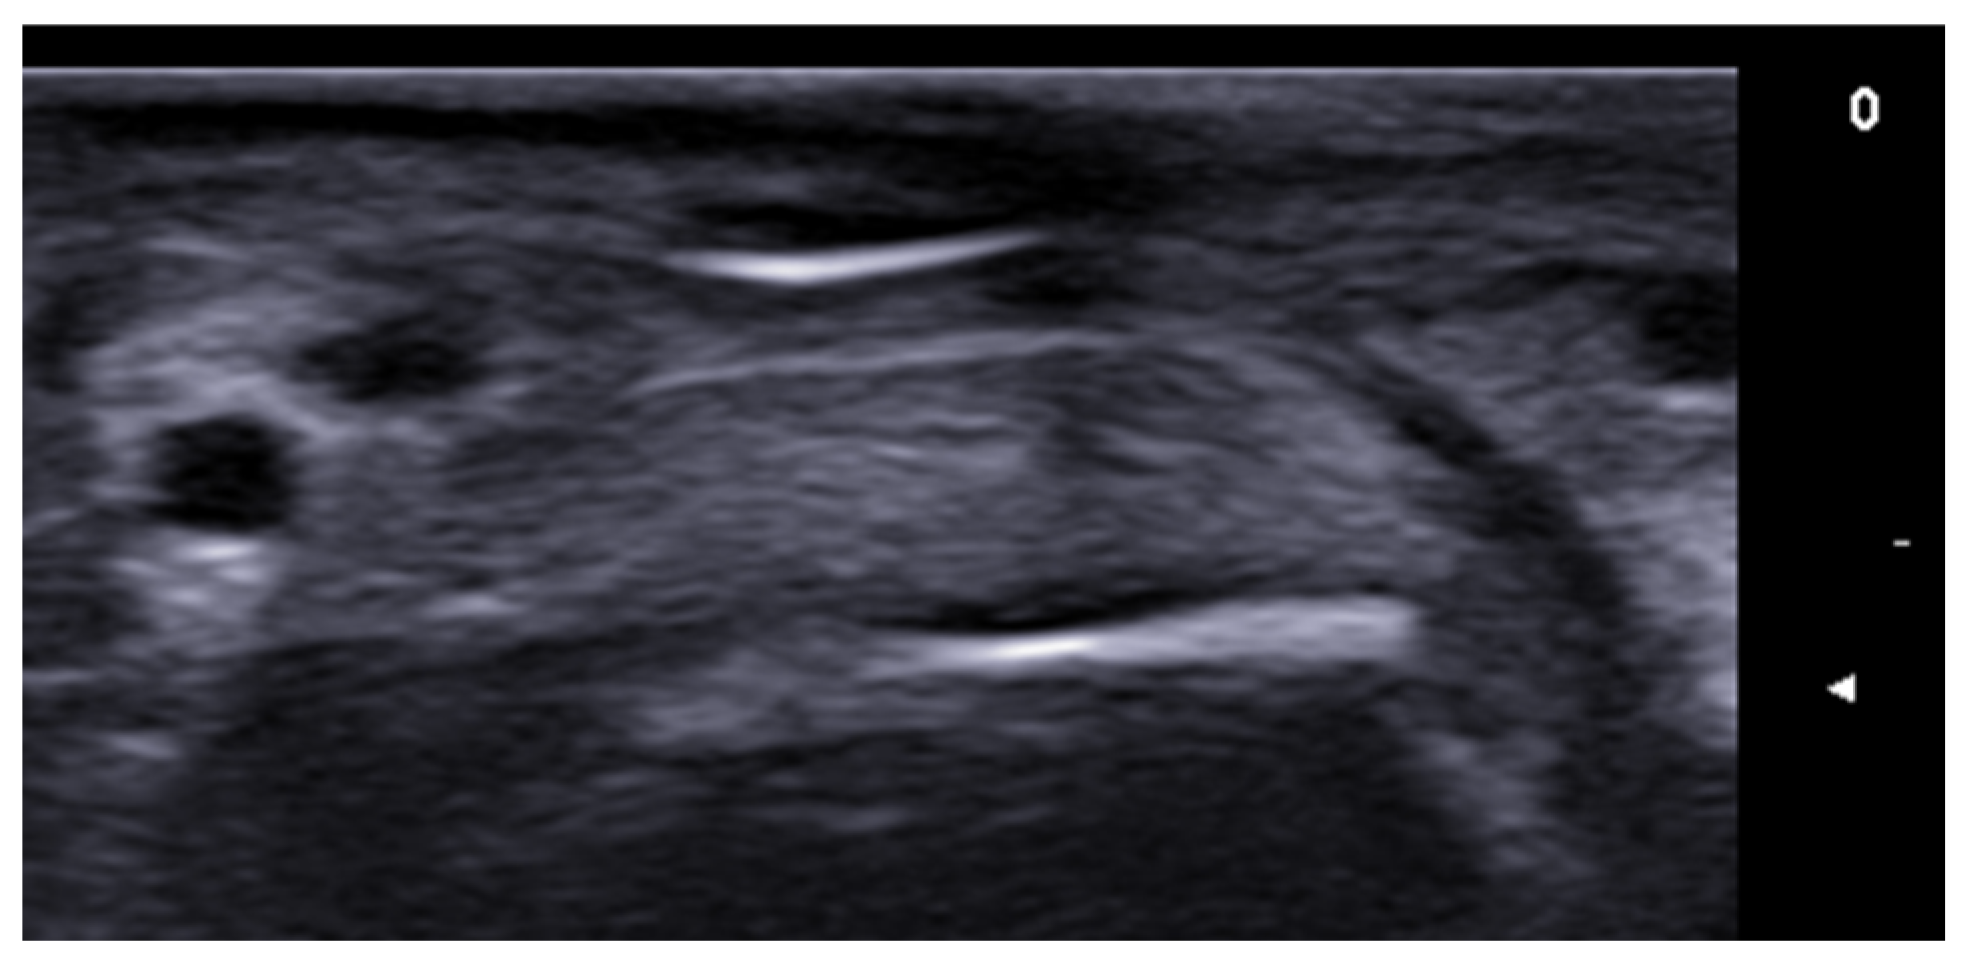

- Bouer, M.; Rodriguez-Bandera, A.I.; Albizuri-Prado, F.; Lobos, A.; Gubeling, W.; Wortsman, X. Real-time high-frequency colour Doppler ultrasound detection of cutaneous Dermatobia hominis myiasis. J. Eur. Acad. Dermatol. Venereol. 2016, 30, e180–e181. [Google Scholar] [CrossRef] [PubMed]